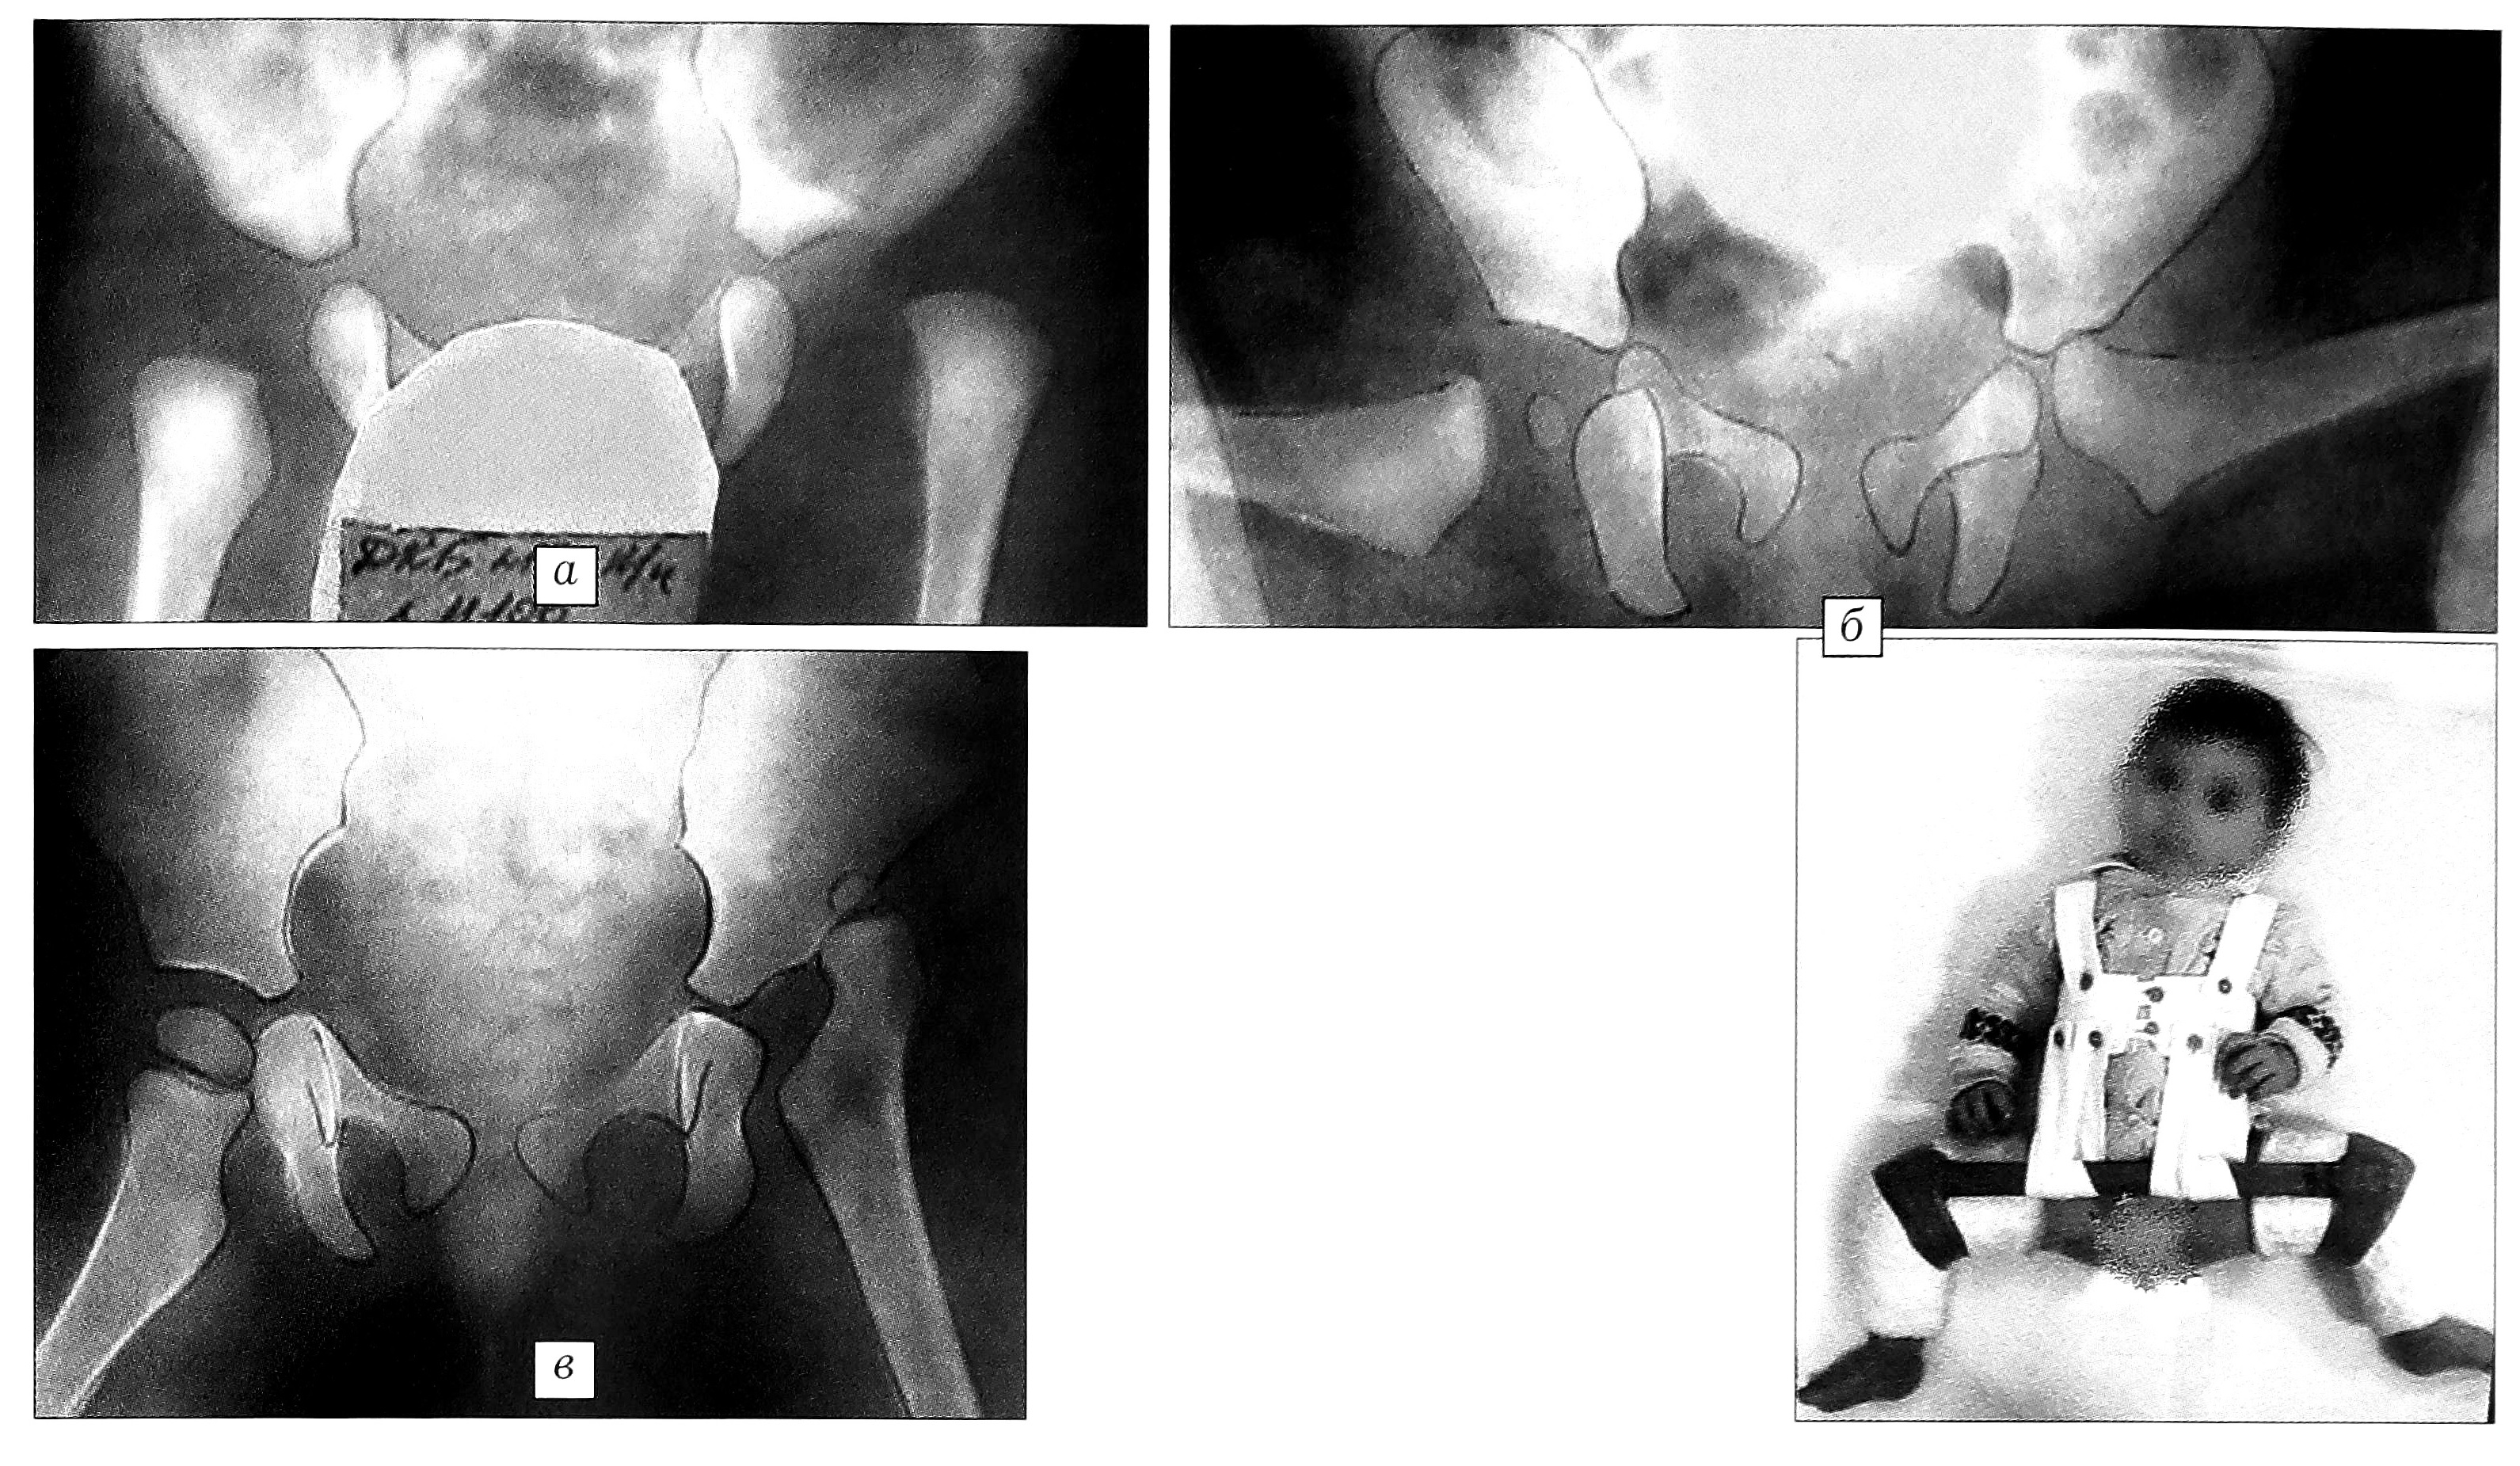

Рис. 2. Пример неадекватного лечения в отводящей шине. Больная Д., диагноз: врожденный надацетабулярный вывих бедер. а — в возрасте 1 мес; б — рентгенологический контроль в возрасте 7 мес в функциональной гипсовой повязке: головка левого бедра располагается за задним краем вертлужной впадины; в — при обращении в ЦИТО в возрасте 1 года 3 мес: вывих в левом тазобедренном суставе сохраняется.

Анализ случаев неустраненного вывиха бедра при лечении с помощью подушки Фрейка выявил, кроме того, несоблюдение показаний к применению этого ортопедического пособия — назначение его детям с высоким смещением головки бедра. Очевидно, что фиксация нижних конечностей подушкой Фрейка целесообразна только при дисплазии тазобедренного сустава без краниального смещения головки бедра. При истинном же вывихе, устранив контрактуру и добившись полного разведения бедер, вправить головку в вертлужную впадину в таком положении не удастся (рис. 1). Применение отводящей шины может быть оправданно также при наличии только дисплазии тазобедренного сустава без децентрации головки бедра. В других случаях лечение этим методом бесперспективно и, следовательно, ошибочно. Примером может служить следующее наблюдение. Больной Д. с двусторонним врожденным вывихом бедер при надацетабулярном расположении головок бедренных костей по месту жительства было назначено лечение в отводящей шине. Контрольная рентгенография показала, что головки бедренных костей располагаются вне вертлужных впадин, однако фиксация в отводящей шине продолжалась. При обращении в ЦИТО в возрасте 7 мес надацетабулярный двусторонний вывих сохранялся (рис. 2).